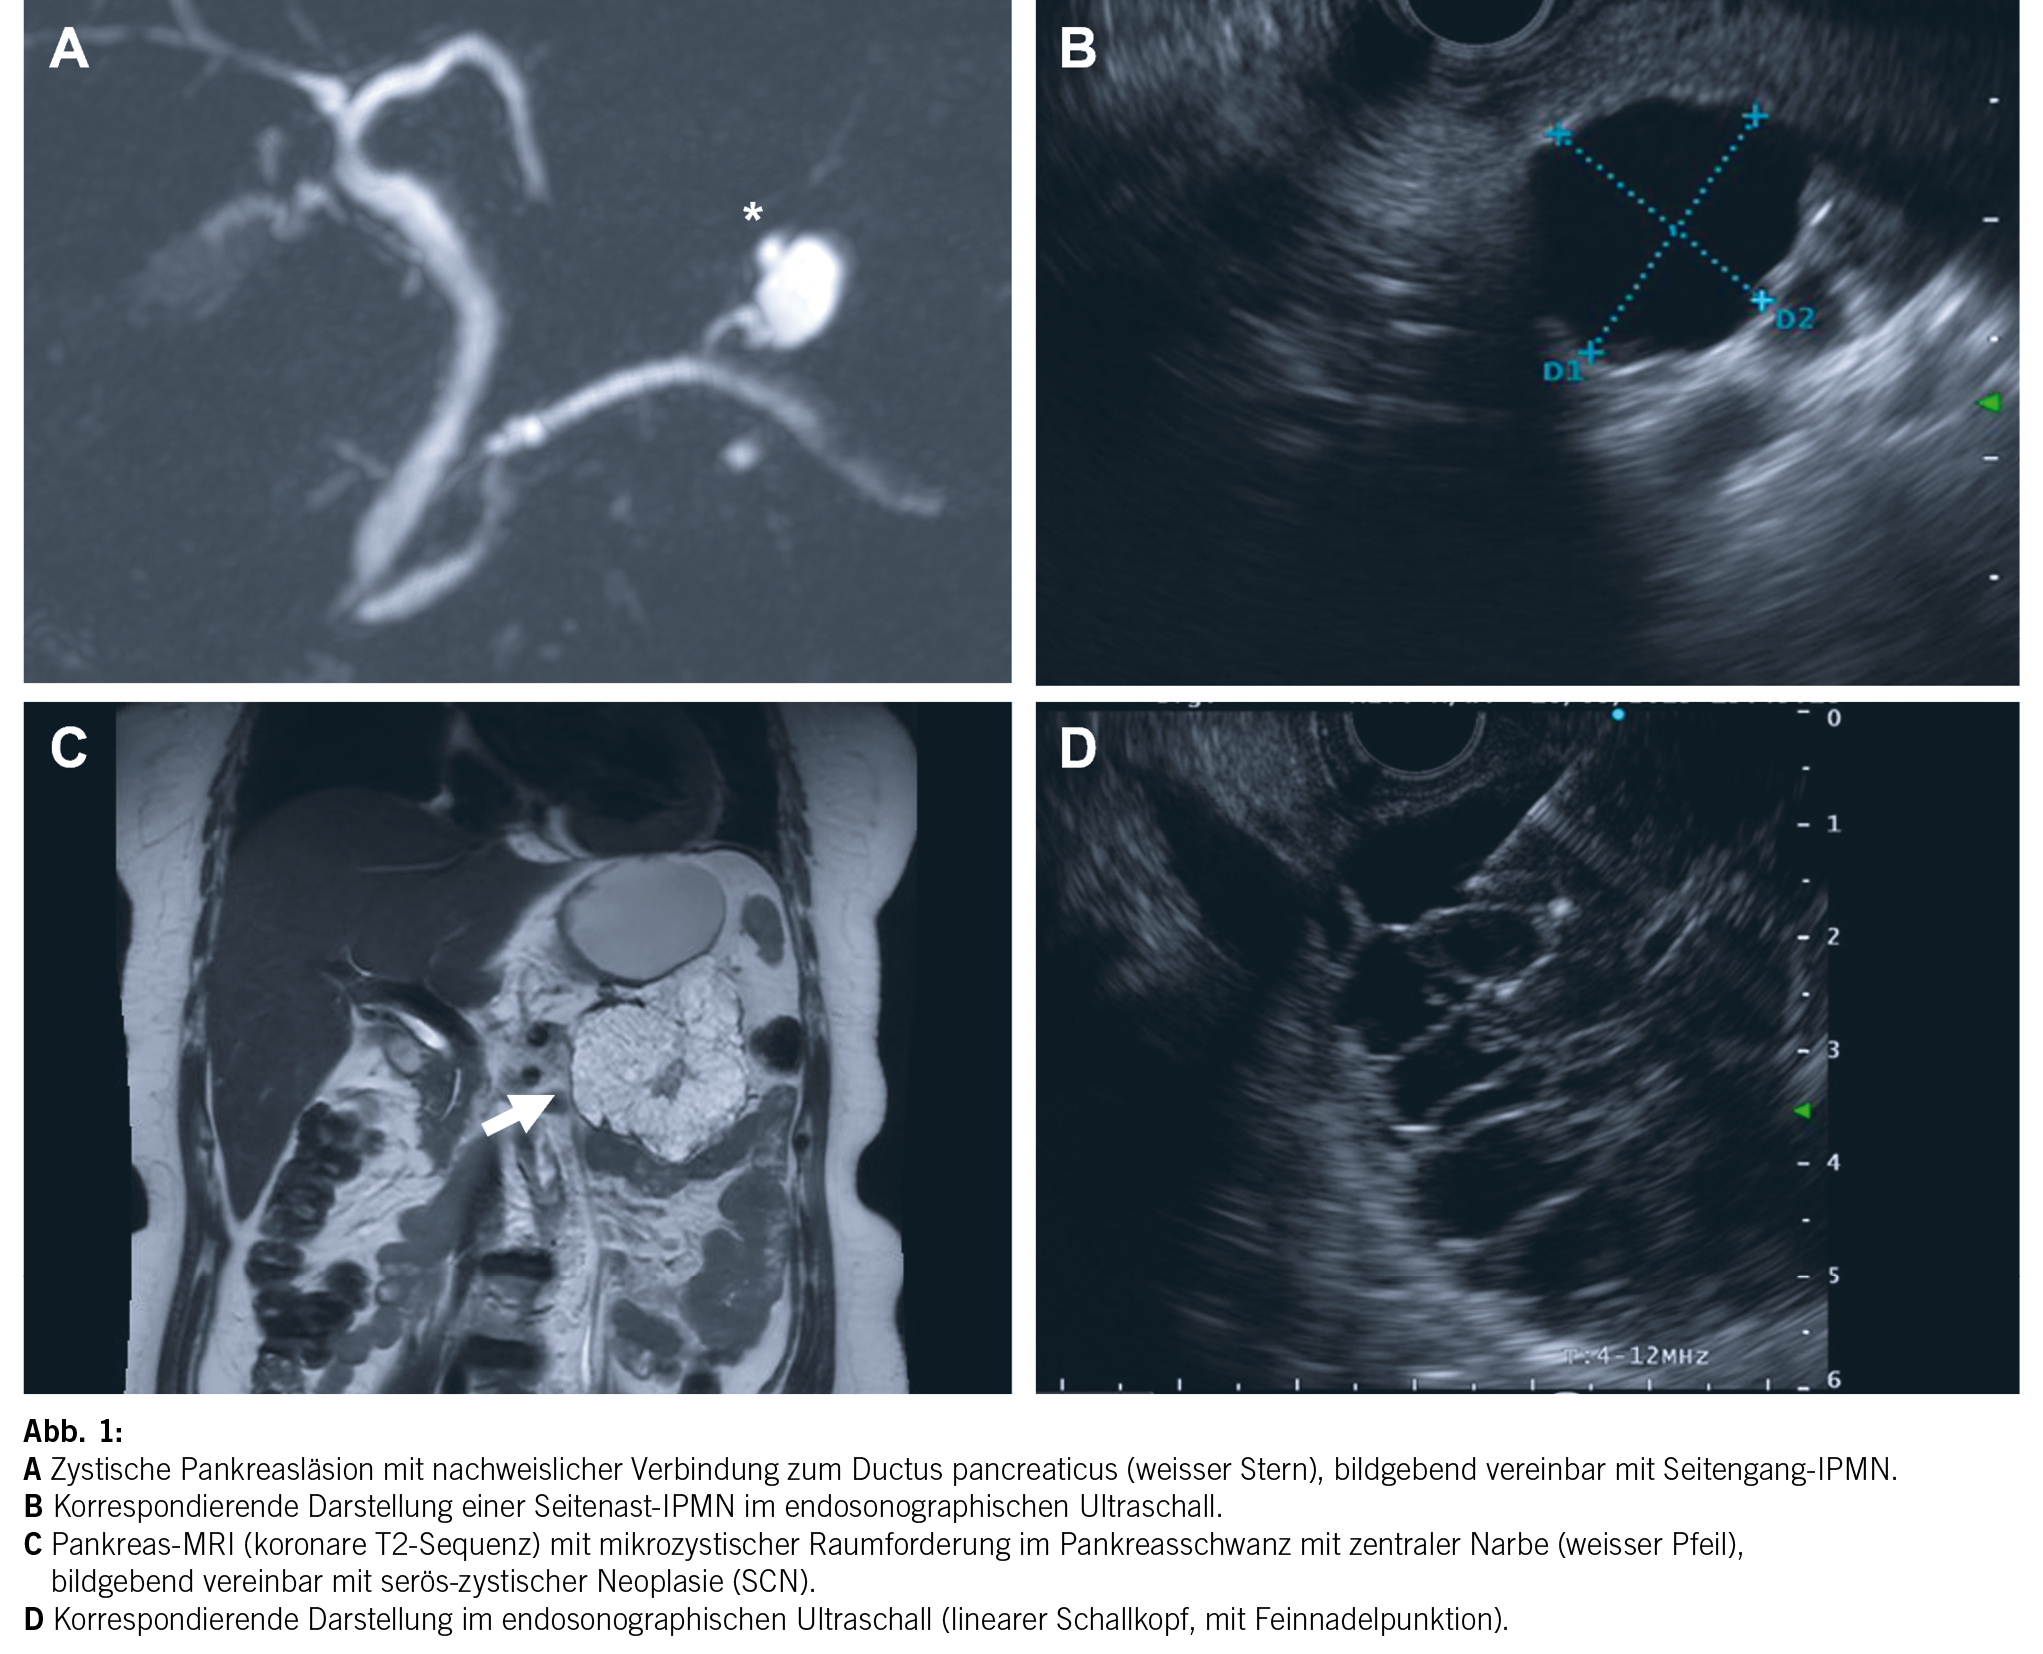

Nebst der Charakterisierung einer zystischen Pankreasläsion ist es auch Aufgabe der Radiologie, nach bildgebenden Zeichen zu suchen, welche auf ein erhöhtes Malignitätsrisiko weisen. Diese bildgebenden Zeichen werden in verschiedenen Leitlinien meist in einem zwei- oder mehrstufigen System abgebildet. In den European evidence-based guidelines on pancreatic cystic neoplasms (11) werden bei radiologisch vermuteter IPMN folgende bildgebende Zeichen als «relative Indikation für Chirurgie» bezeichnet (Abb. 2): Wachstumsrate der zystischen Läsion von ≥ 5 mm/Jahr, eine Dilatation des Pankreashauptganges von 5–9.9 mm, Zystendurchmesser von ≥ 4 cm und kontrastmittelaufnehmende murale Knoten von < 5 mm.

In den letzten Jahren wurden verschiedene Leitlinien zur Surveillance von Pankreaszysten, im speziellen IPMN, publiziert. Zuletzt wurde im Dezember 2023 eine weitere revidierte Version der «Fukuoka»-Leitlinien veröffentlicht (13), in welcher die Rolle der EUS noch etwas stärker gewichtet und ein adaptierter Abklärungsalgorithmus vorgeschlagen wird. Im Zentrum dieser Publikationen stehen radiologische Merkmale, welche auf ein klinisch signifikantes Malignitätsrisiko weisen. Da Pankreasresektionen im Allgemeinen mit einer verhältnismässig hohen Morbidität vergesellschaftet sind, sollten die Leitlinien gleichzeitig unnötige Resektionen verhindern. Anhand von klinischen Zeichen (u. a. Ikterus, Pankreatitis), radiologischen Befunden (z. B. Zystengrösse, Weite D. pancreaticus, Noduli), Tumormarker (CA19-9) und in selektiven Fällen zytologischen oder histologischen Untersuchungen wird versucht, eine Risikostratifikation vorzunehmen.

Dabei bestehen insbesondere bezüglich der Indikationsstellung zur Resektion resp. Durchführung der Surveillance bezüglich Modalität, dem Intervall und der absoluten Dauer der Nachsorge deutliche Unterschiede.

Die meistverwendeten Guidelines sind die

- Revised International Consensus Guidelines (Fukuoka/Kyoto-Guidelines) (13, 14)

- European evidence-based guidelines on pancreatic cystic neoplasms (11)

- American Gastroenterology Association Guidelines (15)

Die Guidelines haben gemeinsam, dass sie zur Entdeckung High-grade-Dysplasien oder invasiver Karzinome eine relativ hohe Sensitivität besitzen, leider aber eine geringe Spezifität aufweisen. Dies führt tendenziell zu einer Überbehandlung der Patienten (17). Ein weiteres Problem in der Behandlung der Pankreaszysten ist die ungenügende Adhärenz zu den Guidelines. Daten aus der Literatur zeigen, dass nur ca. 2/3 aller der Patienten mit bekannten Pankreaszysten einen adäquaten Follow-up erhalten (18). Einen sehr lesenswerten Überblick über die verschiedenen Leitlinien resp. deren Unterschiede bietet die Arbeit von Aziz et al. (19).

Um ein strukturiertes Follow-up zu gewährleisten, aber auch da es sich um potenzielle Krebserkrankungen handelt, sehen wir eine interdisziplinäre Diskussion im Rahmen eines «Pankreaszystenboard» als empfehlenswert. Diese Diskussion soll einerseits unnötige Resektionen verhindern und andererseits eine adäquate und verhältnismässige Surveillance sicherstellen.